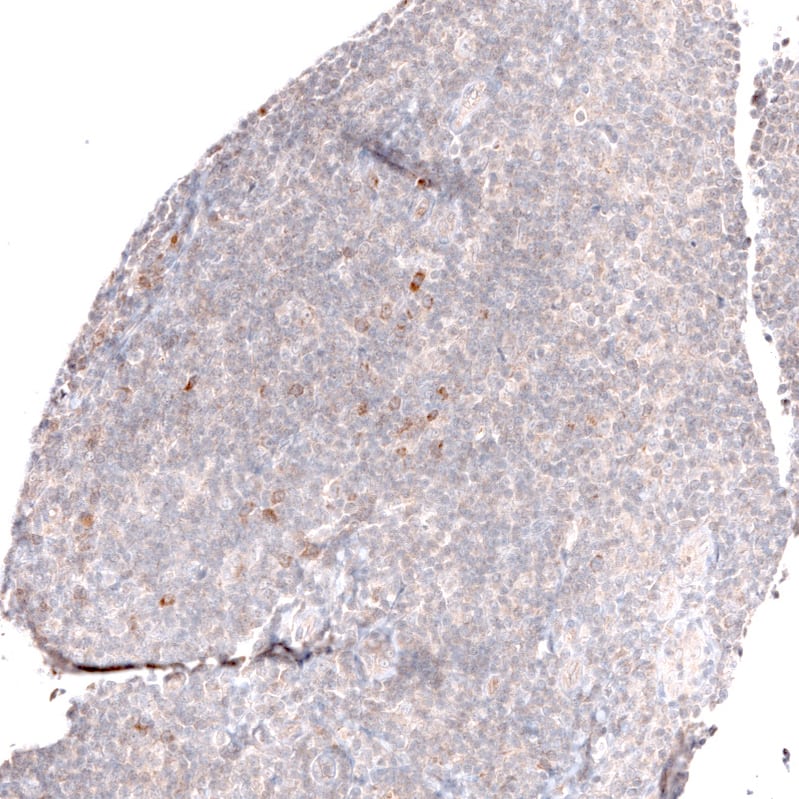

Staining of human cerebral cortex shows moderate cytoplasmic and membranous positivity in neurons and neuropil.